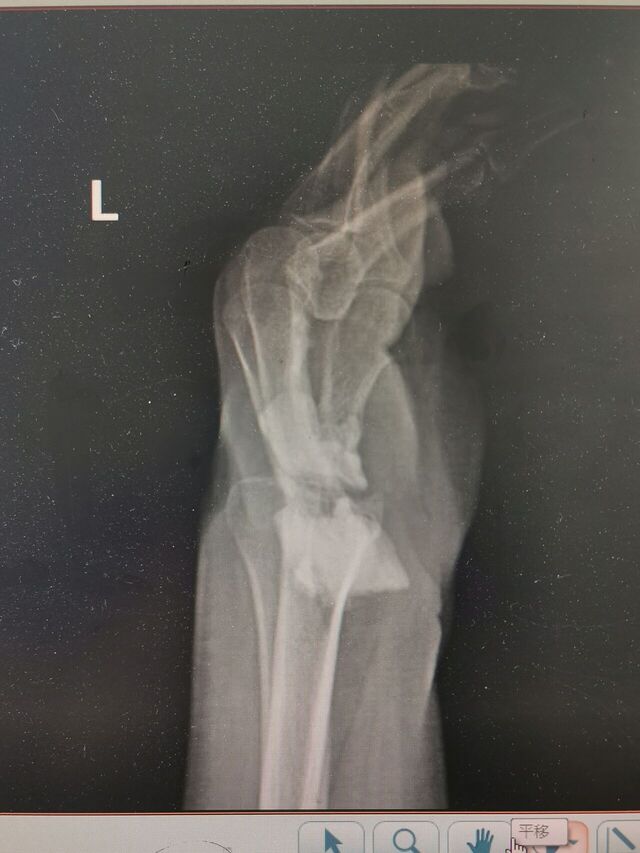

明天一台S-K手术

患者是断腕再植术后

旋转功能受限

活动范围旋前30°-0-0°旋后